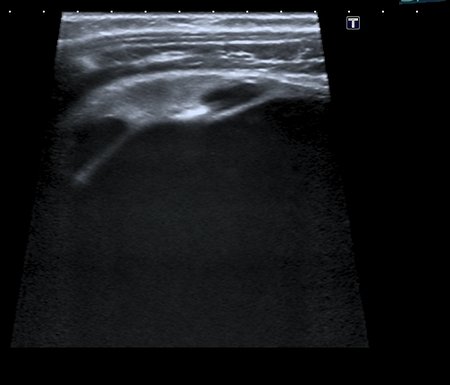

Ещё картинки гидронефроза у ребёнка 6 - ти месяцев, спутать такой гидронефрозище с синусной кистой сложно, а вот с кистой брюшной полости - запросто

- Сканирование высокочастотным датчиком - резидуальная паренхима